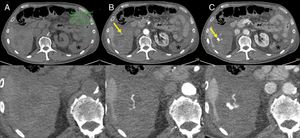

Figure 6.Intratumoral haemorrhage in a patient with a gastrointestinal stromal tumour treated with imatinib. Abdominal CT angiography showing extravasation of intravenous contrast in the arterial phase (B) which increases in the venous phase (C), probably secondary to active intralesional arterial haemorrhage in the perihepatic implant (arrows). Haemoperitoneum (stars) can also be seen. (A) Phase without contrast (shows a region of interest in the left flank with an average density of 30 UH).